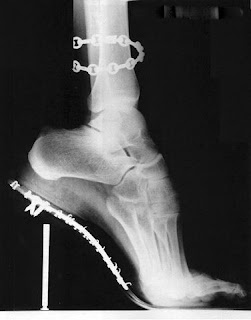

If you believe have a foot problem and do not currently see a podiatrist, call one of our six locations to make an appointment.